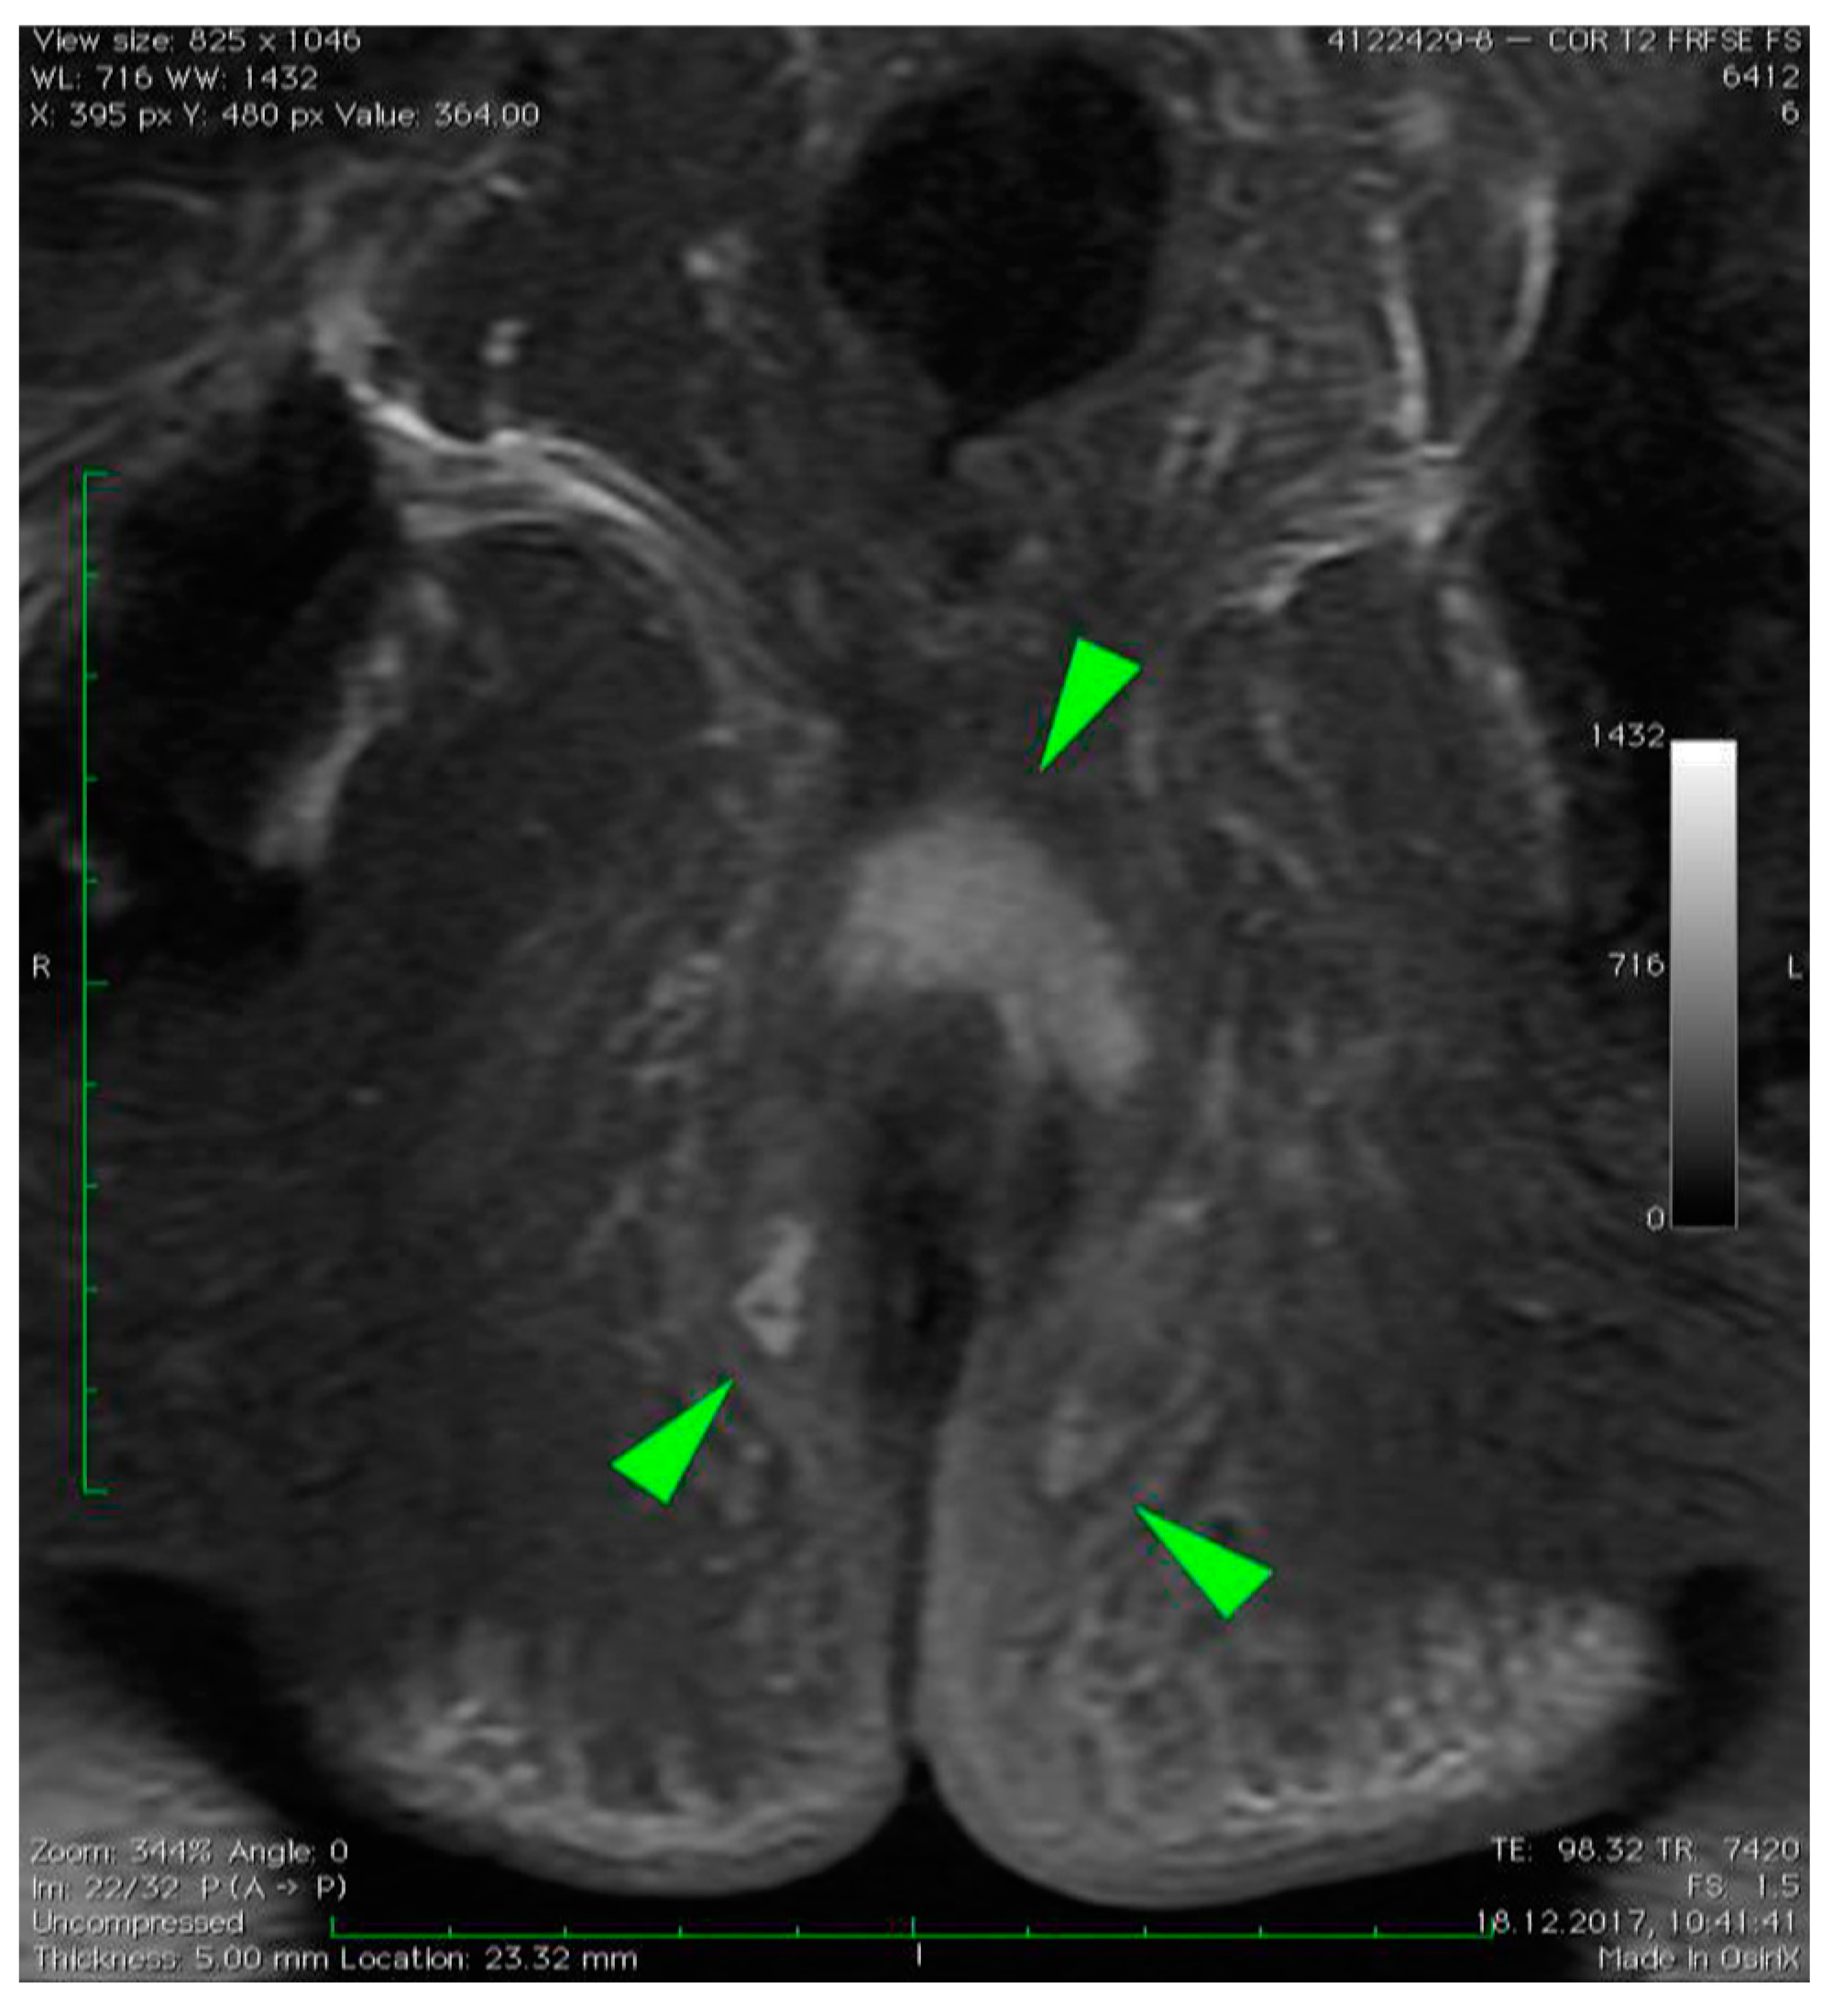

3. Case Presentation